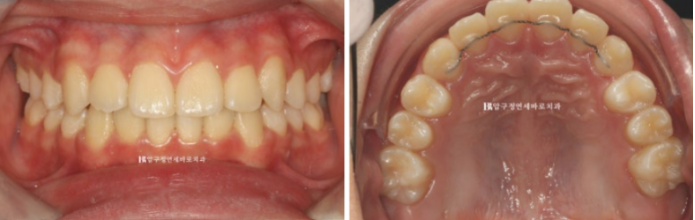

덧니 공간을 마련하고 송곳니를 배열했습니다.

처음과 끝

악궁이 약간 찌그러져 있었지만 배열 후 좋아졌습니다.

덧니가 온전히 제자리를 찾았습니다.

장치 제작기간을 제외하고 실제로 덧니 인비절라인 교정 장치 긴 기간은 1년 입니다.

치료 전 후 자료입니다.